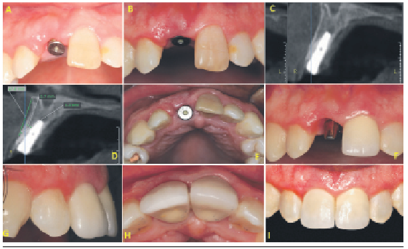

Al examen clínico intraoral se evidenció escasas lesiones cariosas y una leve inflamación gingival. A nivel del sector anterosuperior se observó al incisivo central superior derecho fracturado y con presencia de crecimiento gingival a nivel del fragmento radicular evidenciable al momento de sonreír (Figura 1A y 1B). El examen radiográfico del sector anterior evidenció la ausencia de la corona clínica sin patologías a nivel de la zona periradicular (Figura 1C), el examen tomográfico mostró anchos y altura apropiadas para la colocación de un implante dental (Figura 1D).

Luego de 10 días de posoperatorio la cicatrización del tejido blando fue adecuada no observando complicaciones (Figura 3A). Luego de seis meses de cicatrización no se observó movilidad del implante dental (Figura 3B), tampoco de imágenes radiolúcidas alrededor del implante dental (Figuras 3C y 3D); por el contrario se evidenció que el grosor de la cortical vestibular se conservo en 1mm (Figura 3D). Se procedió a instalar un pilar y corona provisional (Figura 3E y 3F), en la cual con incrementos de resina en la zona crítica y subcrítica se optimizó el perfil de emergencia (Figura 3G). Colocado el pilar definitivo en el implante se procedió a cementar una corona metal cerámica (Figuras 3H y 3I). Se optó por la cementación debido a que son pocas las diferencias entre coronas cementadas o atornilladas sobre el comportamiento del hueso marginal peri-implante y del tejido blando periimplantario en el sector anterior. Luego de seis meses de control se registró un segundo examen tomográfico. Se evidenció la preservación del ancho del reborde alveolar, así como la altura y grosor de la cortical vestibular sin patologías a nivel del fragmento radicular vestibular. Las mediciones tomográficas fueron realizadas desde el borde más vestibular del hueso maxilar hasta la superficie más externa del implante en los puntos cervical, medio y apical (Figura 3D).